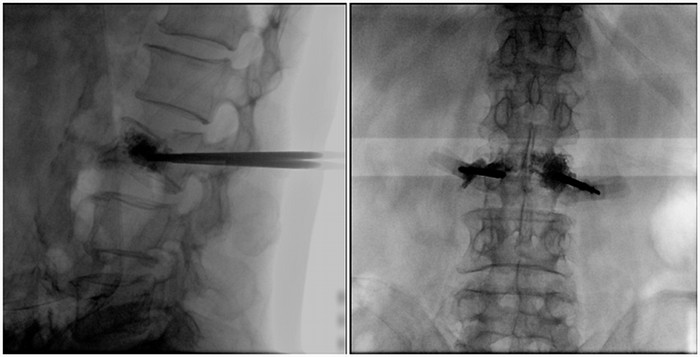

術中切口5毫米,在大平板C臂機的透視指引下,確定了進針的方向及進針的深度。經椎弓根向椎體置管,建立通道,插入骨擴張器(球囊)。球囊擴張恢復椎體高度,并在椎體內形成空腔,確定骨水泥的注入劑量,并注入骨水泥觀察其擴散情況。

大平板C臂機臨床圖像

市面上主流的小C大多采用21CM×21CM的平板或者影像增強器,成像范圍較小,一般可成像3.5節腰椎,確定傷椎可能需要進行多次拍攝。普愛醫療大平板C臂機采用30CM×30CM的平板探測器,一般可一次性成像5節腰椎,呈現更廣闊的視野。使醫生一次性全面地觀察到傷椎及周圍椎體情況,使得手術效率更高、更準確。如果您想采購,或了解這款大平板C臂機技術參數,歡迎咨詢400-025-6366。